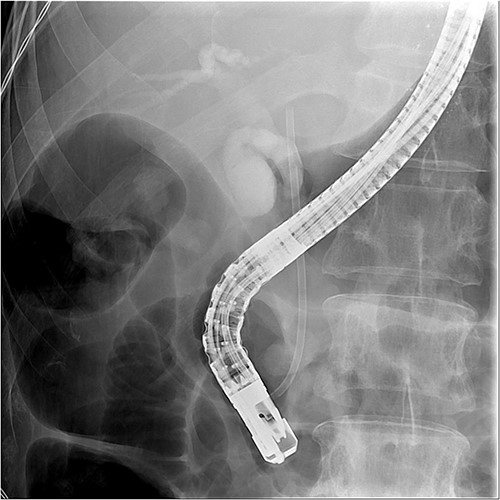

And then, a 7 French bostone scientific plastic stent was inserted over the guide wire for bile diversion. However, hemobilia was noted to be draining out from the stent right after. After reviewing the image, we realised that PVC was probably made (Fig. 3). After discussing with the general surgeon, we decided to arrange immediate surgical exploration to check for collateral damage and remove the CBD stones for cholangitis resolution. The stent was thus left inside for surgical guidance. Before the surgery, abdomen computed tomography (CT) was done and revealed retained contrast medium in the bile duct (Fig. 4) and malposition of the CBD internal stent with upper portion in the main portal vein (Fig. 5).

Malposition of the CBD internal stent with upper portion in main portal vein.